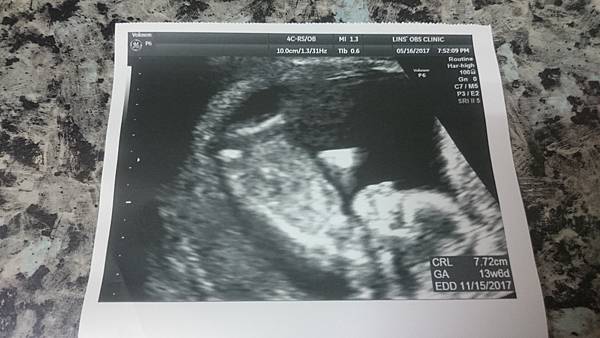

5/19

第二次產檢

醫生說我上次做的檢查皆正常

我的孕吐狀況也好多了

醫生說約再2個禮拜這些狀況就會消失了

8公分的寶寶

說是個頑皮的男孩子呢!

看他一直好動好可愛~~~

我的寶寶